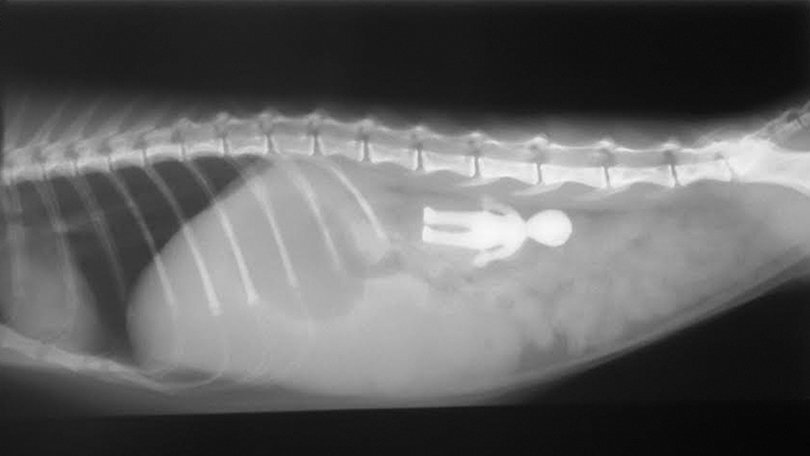

Удаление инородных тел из естественных отверстий